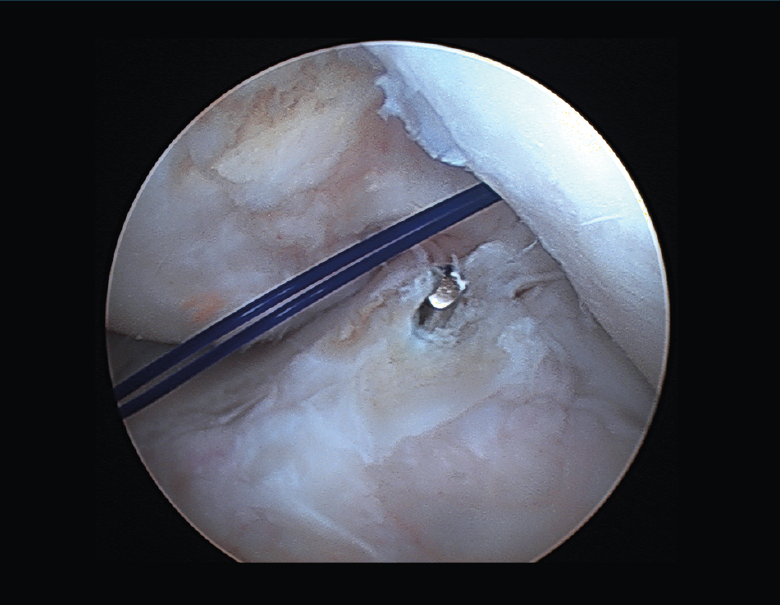

Túnel tibial

Aunque el punto de entrada extraarticular pueda variar, la salida del túnel tibial a nivel intraarticular es fija. Idealmente, esta será sobre el muñón residual del LCA, centrado sobre la espina tibial interna, paralelo al borde posterior del cuerno anterior del menisco externo y 7 mm anterior al ligamento cruzado posterior (LCP) (Figura 14). Jugando con el ángulo de la guía tibial podremos variar la longitud del túnel. El objetivo es permitir que las fibras de la plastia se dispongan de forma inclinada y paralelas a la línea de Blumensaat en extensión (Figura 15).

Figura 14. Aguja guía en la huella tibial del ligamento cruzado anterior.

Suponiendo que la colocación de los túneles sea correcta, se tensará la plastia entre 0 y 20° de flexión. Esta posición permitirá conseguir la alineación sagital tibial sin restringir la amplitud de movimientos en extensión. Si el injerto de LCA se tensara en mayor flexión, se debe comprobar la extensión completa de la rodilla meticulosamente para asegurar que la amplitud de movimientos es completa.